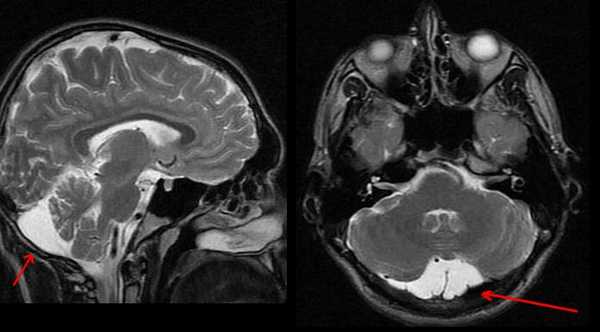

МРТ головного мозга. Т1-взвешенная сагиттальная МРТ. Арахноидальная киста в области большого затылочного отверстия.

Арахноидальные кисты представляют собой скопление ликвора между листками расщепленной паутинной оболочки. Арахноидальная киста обычно не сопровождается другими мальформациями. Незначительная часть арахноидальных кист имеет приобретенное происхождение - следствие лептоменингита, операции или кровоизлияния. Частота составляет около 1% от внутричерепных образований. Соотношение полов М:Ж, как 4:1. Типичная локализация - средняя черепная ямка (в области Сильвиевой борозды 50%), межполушарная щель, мосто-мозжечковый угол (11%), за скатом или на уровне четверохолмия (10%), в области червя мозжечка (9%), реже в области межножковой и предмостовой цистерн (3%), а также супраселлярной и хиазмальной цистерн. В зависимости от размера предложено делить кисты на 3 типа (Galassi, 2006), что однако, не имеет практического значения. Ретроцеребеллярная арахноидальная киста довольно часто встречаются за мозжечком и отличима от mega cisterna только по неизменённой задней черепной ямке. При МРТ головного мозга содержимое кисты чисто ликворное, стенки гладкие, чётко очерченные, внутри кисты могут быть перегородки. Мелкие арахноидальные кисты очень трудно увидеть при МРТ головного мозга. Меняя ширину окна и его уровень на Т1-зависимых МРТ изображениях можно заметить, что киста чуть светлее ликвора. Дифференциальная диагностика с эпидермальными кистами лучше осуществляется с помощью МРТ последовательности FLAIR. На них при МРТ головного мозга эпидермальные кисты становятся яркими, в отличие от гипоинтенсивных арахноидальных. Вероятно, вариантом арахноидальной кисты является нейроэпителиальная киста, которая при МРТ головного мозга имеет типичное расположение в области хориоидальной щели.